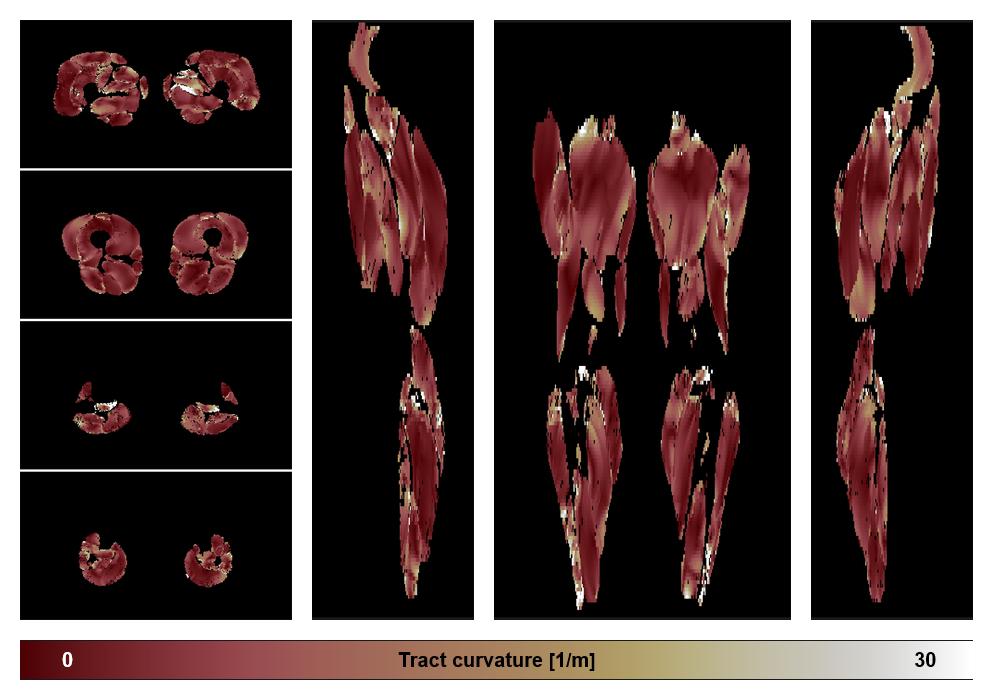

• Muscle fiber curvature map

Muscle fiber tract curvature map based on whole leg DTI based fiber tractography.